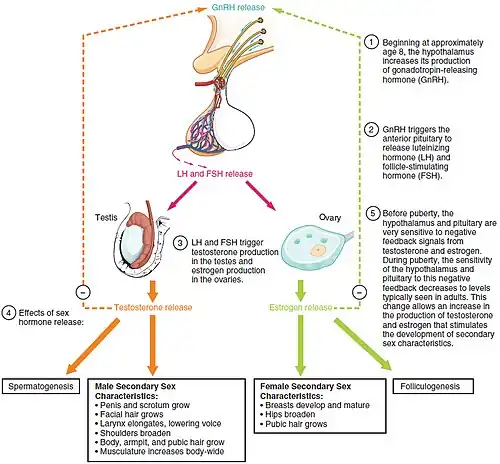

Luteinizing hormone (LH, also known as luteinising hormone,[1] lutropin and sometimes lutrophin[2]) is a hormone produced by gonadotropic cells in the anterior pituitary gland. The production of LH is regulated by gonadotropin-releasing hormone (GnRH) from the hypothalamus.[3] In females, an acute rise of LH known as an LH surge, triggers ovulation[4] and development of the corpus luteum. In males, where LH had also been called interstitial cell–stimulating hormone (ICSH),[5] it stimulates Leydig cell production of testosterone.[4] It acts synergistically with follicle-stimulating hormone (FSH).

In both males and females, LH works upon endocrine cells in the gonads to produce androgens.

Effects in females

LH supports theca cells in the ovaries that provide androgens and hormonal precursors for estradiol production. At the time of menstruation, FSH initiates follicular growth, specifically affecting granulosa cells.[9] With the rise in estrogens, LH receptors are also expressed on the maturing follicle, which causes it to produce more estradiol. Eventually, when the follicle has fully matured, a spike in 17α-hydroxyprogesterone production by the follicle inhibits the production of estrogens. Previously, the preovulatory LH surge was attributed to a decrease in estrogen-mediated negative feedback of GnRH in the hypothalamus, subsequently stimulating the release of LH from the anterior pituitary.[10] More recent studies, however, attribute the LH surge to positive feedback from estradiol after production by the dominant follicle exceeds a certain threshold. Exceptionally high levels of estradiol induce hypothalamic production of progesterone, which stimulates elevated GnRH secretion, triggering a surge in LH.[11] The increase in LH production only lasts for 24 to 48 hours. This "LH surge" triggers ovulation, thereby not only releasing the egg from the follicle, but also initiating the conversion of the residual follicle into a corpus luteum that, in turn, produces progesterone to prepare the endometrium for a possible implantation. LH is necessary to maintain luteal function for the second two weeks of the menstrual cycle. If pregnancy occurs, LH levels will decrease, and luteal function will instead be maintained by the action of hCG (human chorionic gonadotropin), a hormone very similar to LH but secreted from the new placenta.

Effects in males

LH acts upon the Leydig cells of the testis and is regulated by gonadotropin-releasing hormone (GnRH).[13] The Leydig cells produce testosterone under the control of LH. LH binds to LH receptors on the membrane surface of Leydig cells. Binding to this receptor causes an increase in cyclic adenosine monophosphate (cAMP), a secondary messenger, which allows cholesterol to translocate into the mitochondria. Within the mitochondria, cholesterol is converted to pregnenolone by CYP11A1.[14] Pregnenolone is then converted to dehydroepiandrosterone (DHEA).[15] DHEA is then converted to androstenedione by 3β-hydroxysteroid dehydrogenase (3β-HSD)[16] and then finally converted to testosterone by 17β-hydroxysteroid dehydrogenase (HSD17B). The onset of puberty is controlled by two major hormones: FSH initiates spermatogenesis and LH signals the release of testosterone,[17] an androgen that exerts both endocrine activity and intratesticular activity on spermatogenesis.

LH is released from the pituitary gland, and is controlled by pulses of gonadotropin-releasing hormone. When bloodstream testosterone levels are low, the pituitary gland is stimulated to release LH.[13] As the levels of testosterone increase, it will act on the pituitary through a negative feedback loop and inhibit the release of GnRH and LH consequently.[18] Androgens (including testosterone and dihydrotestosterone) inhibit monoamine oxidase (MAO) in the pineal gland, leading to increased melatonin and reduced LH and FSH by melatonin-induced increase of Gonadotropin-Inhibitory Hormone (GnIH)[19] synthesis and secretion. Testosterone can also be aromatized into estradiol (E2) to inhibit LH. E2 decreases pulse amplitude and responsiveness to GnRH from the hypothalamus onto the pituitary.[20]